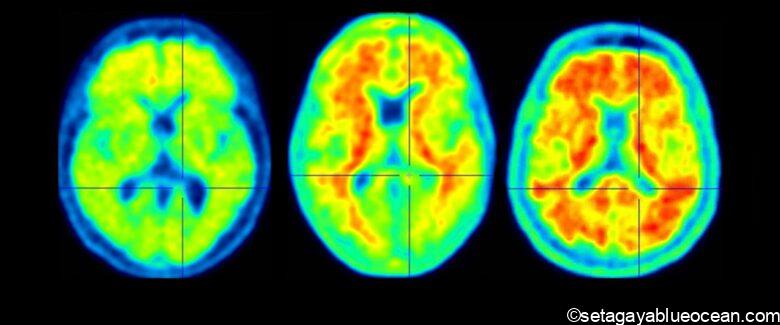

It is believed to be caused by the accumulation of an abnormal protein called amyloid-β (Aβ) in the brain.

While existing dementia drugs work to alleviate symptoms by stimulating nerve function, Lecanemab aims to eliminate Aβ, the cause of the disease, and suppress the progression of the disease.